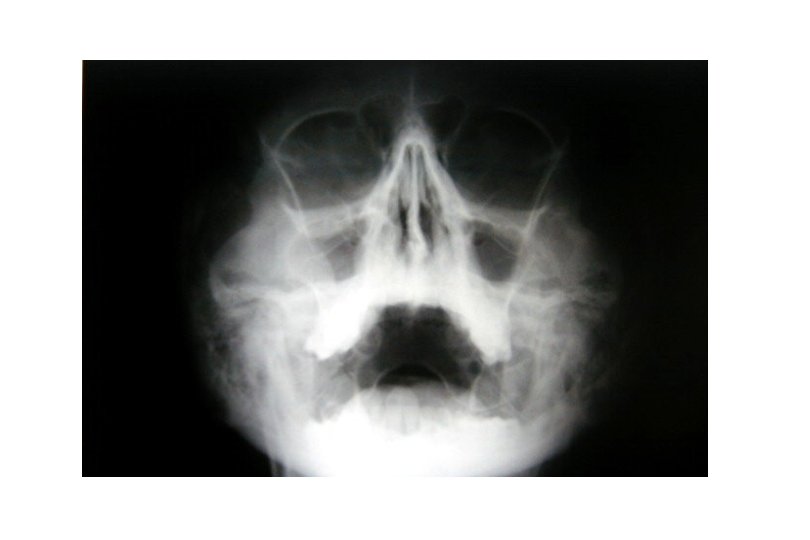

Sinusitis: Clínica * Rinorrea mucopurulenta persistete * Tos (nocturna) * Congestión nasal * Voz nasal * Dolores faciales * Cefaleas * Estrías sanguinolentas con el moco * Espasticidad bronquial repetida * RX y TC: -Engrosamiento y opacificación de las mucosas. -Niveles hidroaéreos